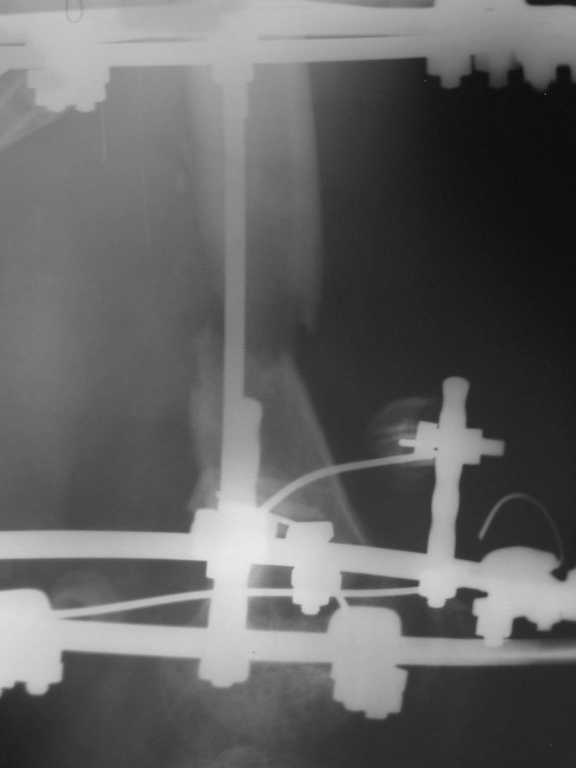

Уважаемые коллеги. Возникли затруднения с выбором оптимальной тактики ведения и лечения больного с огнестерльным ранением правого бедра. Пациент лечился в областной больнице в течении почти двух месяцев, после чего был отправлен на амбулаторное лечение. Травма была получена на Новый Год, прострелили правое бедро сигнальной ракетницей, был многооскольчатый перелом правой бедренной кости, сквозное ранение мягких тканей с обширными ожогами правой и левой конечностей 2 - 3 степени. При поступлении была выполнена ПХО раны, ожогов, наложены асептические повязки. Через две недели наожен аппарат Илизарова для постепенной компрессии отломков. На протяжении 1,5 месяцев проводилась компрессия - в результате отломки стали соприкасаться, укорочение конечности составило примерно 6 см. Рана мягких тканей к этому времени практически закрылась. С этим результатом в начале марта больной был отправлен на амбулаторное лечение по месту жительства (см. рентгеннограммы). Ему были даны рекомендации - продолжить компрессию в течении 6 недель по 1,5 мм в неделю, контрольный снимок через месяц. Пациент следовал рекомендациям,продолжал компрессию и в апреле отослал снимки в областную больницу на консультацию(см. рентгенограммы). Ему посоветовали продолжить компрессию еще на месяц. Последние снимки были сделанны в мае и опять он получил рекомендации продолжать компрессию. После этого он пришел ко мне на консультацию с вопросом - что ему делать. Мое мнение: поскольку наблюдается обширный дефект костной ткани, я бы рекомендовал провести оперативное вмешательство и восплнить этот дефект аллотрансплантантом костной ткани. Трансплантант сыграет роль депо минеральных веществ и заодно ускорит восполнение дефекта. А после этого вторым этапом провести уже удлинение конечности. На ваш взгляд какой тактики лучше придерживаться - продлжать компрессию или провести операцию по восполнению дефекта?

Думаю, Вы правы, рано или поздно вопрос о пластике дефекта и восстановлении длины (точнее, выравнивание достигается и укорочением "здоровой" тоже) поднимется, и решать его придётся максимально сразу, т.к. ждать сращения год, потом удлиннять и опять ждать сращения - это не удобства для пациента, а значит и для хирурга. Хотя в каждом монастыре свои порядки... После травмы прошло 5 полных месяцев, и если нет остеомиелита, надо менять остеосинтез на погружной, свободная аутоостеопластика, но... интересный вопрос ко всем! На сколько дистракция отломков бедренной кости должна быть больше имеющегося укорочения? вопрос к Вам - на сколько мобилены т/б и коленный суставы?, нет ли зон выпадения чувствительности, выполнен ли доплер сосудов этой конечности и что это за рана, которая закрылась в феврале?

костная пластика в сочетании с остеосинтезом пластиной DCS или ретроградным гвоздём; а удлиненить конечность можно и за счёт голени, всё это одновременно.